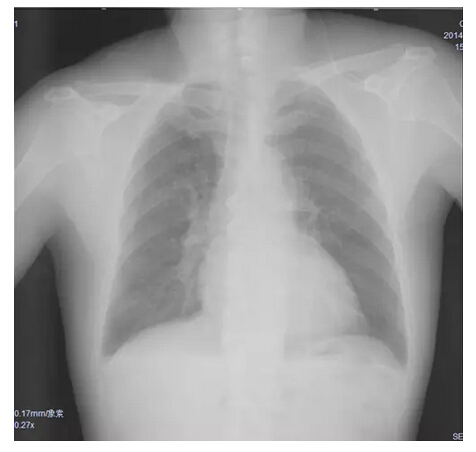

胸片:肺淤血,肺无实变。

![]()